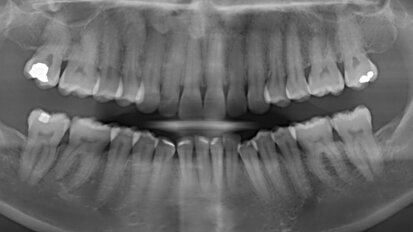

Retence získává nový význam